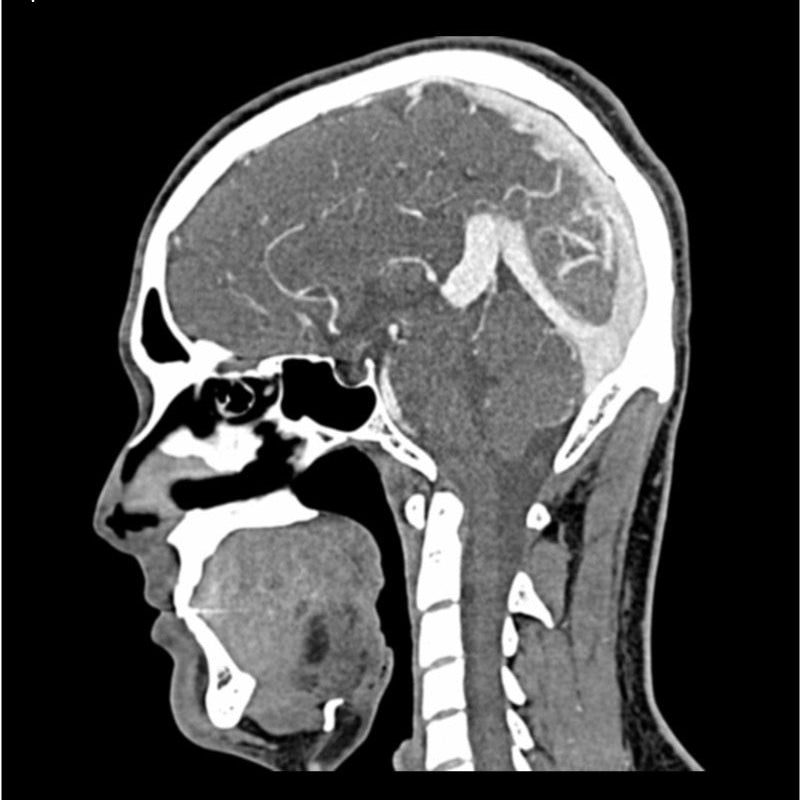

This phantom simulates a contrast medium enhanced head in arterial phase (CT angiography). It covers the vertex to the fifth cervical vertebra. The phantom has 10 low-contrast lesions in the centrum semiovale and the right hemisphere has an arteriovenous malformation.

The phantom can be used in CT (including CBCT) to evaluate and optimize imaging performance and AI-enabled diagnosis. It is also suited for training purposes. The phantom provides a detailed and realistic simulation of vascular structures, soft and bone tissue. Air voids are filled with a cellulose-polymer composite of approx. -160 HU.

- Size: Approx. 19 x 22 x 27 cm